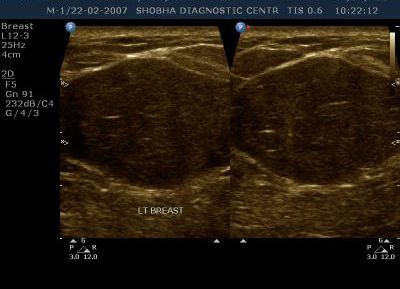

High Resolution Small Part Sonography / Musculoskeletal Sonography

All the superficial parts of the body like neck, thyroid, orbits, breast, any soft tissue swelling are best assessed on ultrasound.